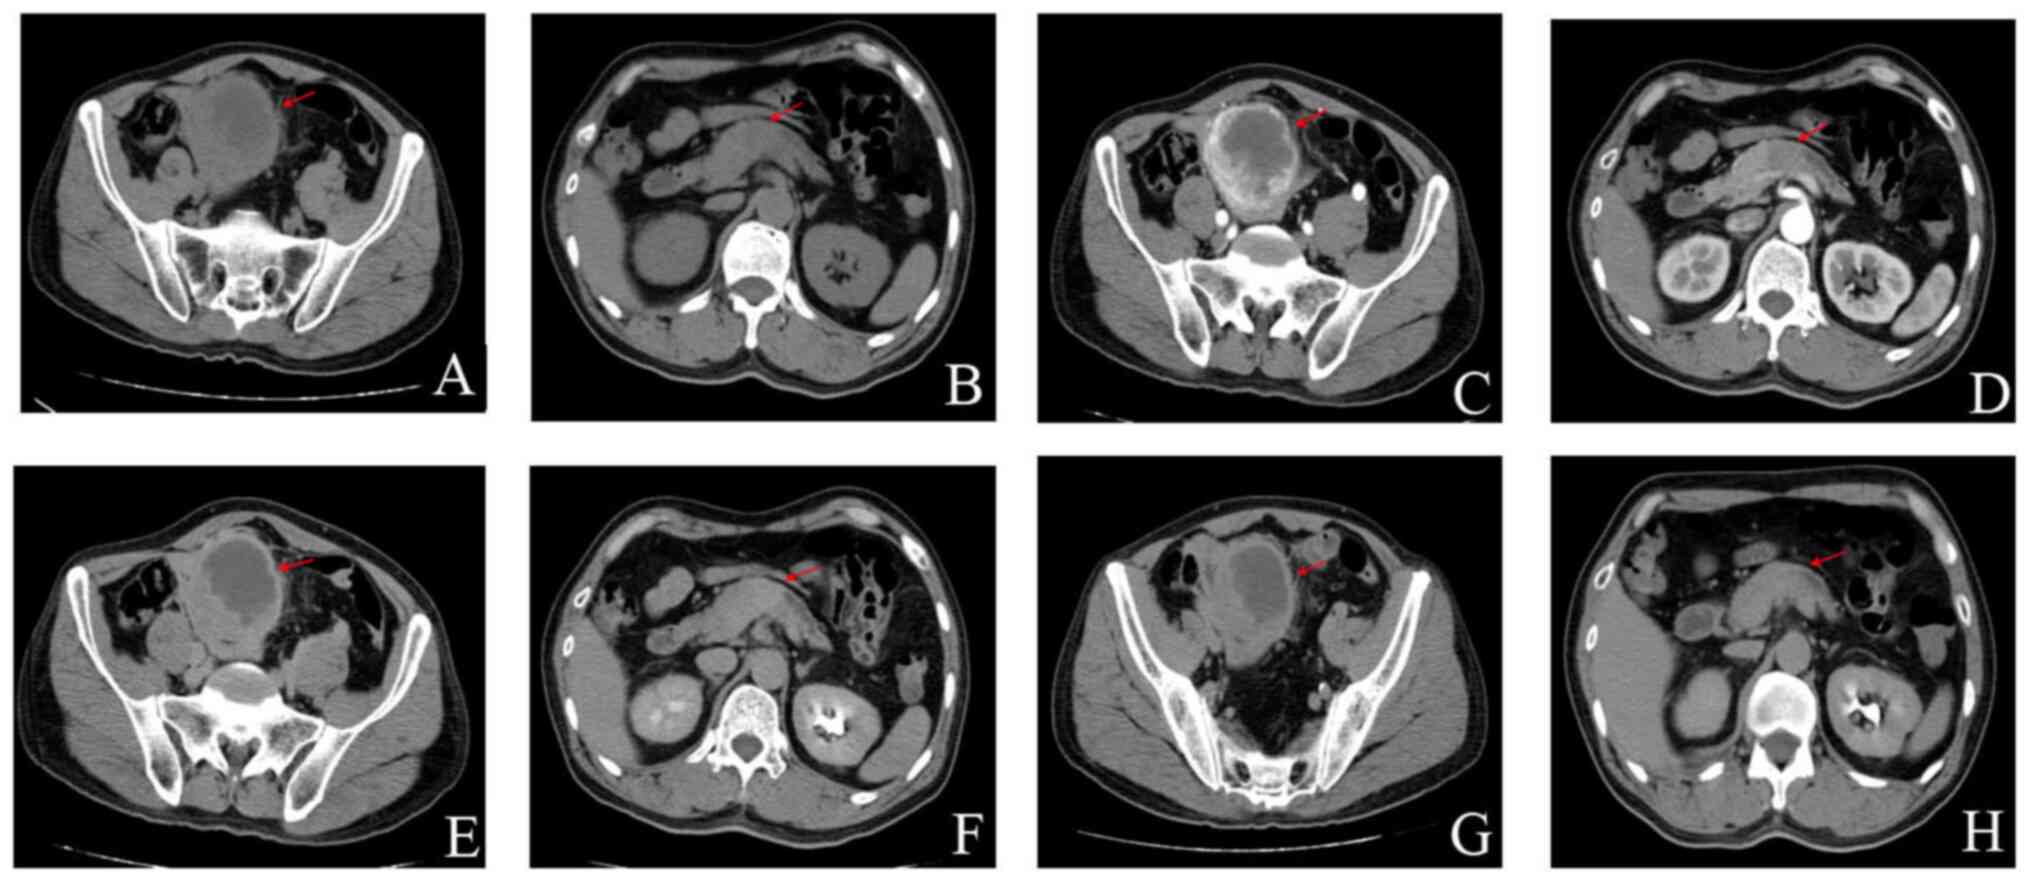

A 54-year-old male patient was admitted to the Yiwu Central Hospital (Yiwu, China) for diagnosis and treatment in June 2018, due to ‘right ureteral calculi found in physical examination for 2 days’. A total of 2 days before admission, a B-ultrasound examination of the patient's urinary system in Yiwu Second People's Hospital (Yiwu, China) showed ‘right upper ureteral calculi and pelvic space occupation’. The patient reported frequent and urgent urination, pain during urination and occasional discomfort in the lower abdomen. Physical examination upon admission revealed a body temperature of 36.9°C, a pulse of 100 bpm, respiration of 19 breaths/min, blood pressure of 104/74 mmHg (1 mmHg=0.133 kPa) and oxygen saturation of 99%. No notable abnormalities were found in the cardiopulmonary examination. Urinary CT results indicated ‘right upper ureteral calculi, dilation of the upper ureter and renal pelvis, low-density lesions of the left kidney and masses in the adnexal right lower abdomen’. An auxiliary examination was performed and routine blood testing revealed a white blood cell count of 12.01×109/l, CRP of 161.10 mg/l and a neutrophil count of 8.90×109/l. Coagulation parameter assessment revealed fibrinogen levels of 6.767 g/l and D-dimer levels of 2,330 mg/l, and the blood type of the patient was Rh-positive B. Urine analysis revealed sedimentary white blood cells at 102/ml and urinary sediment epithelial cells at 13/ml. Biochemical analysis indicated g-glutamyl transferase levels of 353 U/l and alkaline phosphatase levels of 349 U/l. A color Doppler ultrasound of the digestive system showed multiple calculi in the upper right ureter with right hydronephrosis and a left renal cyst with prostatic hyperplasia with calcification. Chest posterior-anterior CT showed no notable substantial lesions. The preliminary diagnoses were right ureteral calculi with hydronephrosis and a pelvic mass. As the nature of the pelvic space occupation was unknown and the routine blood test indicated an inflammatory reaction, broad-spectrum antibacterial drugs for anti-infection treatment were temporarily administered. Subsequently, an enhanced CT of the urinary system showed a pelvic space-occupying lesion, indicating the potential presence of a stromal tumor; due to these data, a puncture biopsy was recommended and space-occupying pancreatic cancer was considered (Fig. 1).

Figure 1.

Enhanced CT scan of the urinary system. (A) Plain CT scan, Pelvic stromal tumor, (B) Plain CT scan, pancreatic cancer, (C) CT enhanced scan of cortical phase, pelvic stromal tumor, (D) CT enhanced scan of cortical phase, pancreatic cancer, (E) CT enhanced scan of medullary phase, pelvic stromal tumor, (F) CT enhanced scan of medullary phase, pancreatic cancer, (G) CT enhanced scan of the excretion period, pelvic stromal tumor and (H) CT enhanced scan of the excretion period, pancreatic cancer. The red arrows indicate the location of the lesion. CT, computerized tomography.

Additionally, the enhanced CT of the urinary system revealed that the distal pancreatic duct was dilated, with body and tail atrophy observed. Calculi were identified in the ventral segment of the right ureter with dilatation of the upper ureter and right renal pelvis, indicating a possible bilateral renal cyst or prostatic hyperplasia. In accordance with the opinion of experts in hepatobiliary surgery, a right indwelling ureteral stent was implanted after anti-infection treatment during urological surgery, and the pancreatic and pelvic space-occupying lesion was treated after infection control by hepatobiliary surgery. Implantation of the right indwelling ureteral stent was successfully performed under local anesthesia with antibiotics and fluid infusion administered as the postoperative treatment for the stent implantation. From these data, a postoperative diagnosis of right ureteral calculus with hydronephrosis, pelvic mass and pancreatic space-occupying lesion was made.